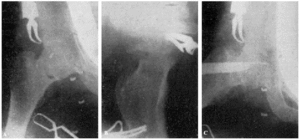

En la actualidad, siguiendo a Rankin, García Díaz y otros autores, también intervenimos las fracturas del cuello del fémur extracapsulares, y como que en ellas permitimos que el paciente abandone el lecho a los quince días de la intervención, acortamos de un modo extraordinario el período de recuperación funcional (fig. 21, A y B).

Figura 19. A y B: obs. núm. 34. Buena colocación del clavo.

Figura 20. A y B: obs. núm. 35. Perfecta colocación del «Kirschner» en ambas proyecciones. C y D: obs. núm. 35. Buena colocación del clavo.

Figura 21. A: obs. núm. 37. Fractura pertrocantérea. B: obs. núm. 37. Reducción y situación del clavo. Sin embargo es preferible, en este tipo de fractura, que el punto de entrada del clavo sea más inferior para que haga más buena presa en el fragmento distal. Un clavo de aletas más anchas en su parte proximal sería muy recomendable en estos casos.